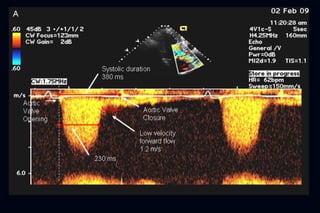

Hallazgos ecocardiográficos

   Una característica típica es el impacto del aumento del

septum en el Doppler del TSVI

   Patrón con contorno de daga

   Dagger shaped spectral Doppler pattern

   Refleja un peak tardío de flujo sistólico a través del TSVI

CW Doppler TSVI

Hallazgos ecocardiográficos  Una característica típica es el impacto del aumento del septum en el Doppler del TSVI  Patrón con contorno de daga  Dagger shaped spectral Doppler pattern  Refleja un peak tardío de flujo sistólico a través del TSVI